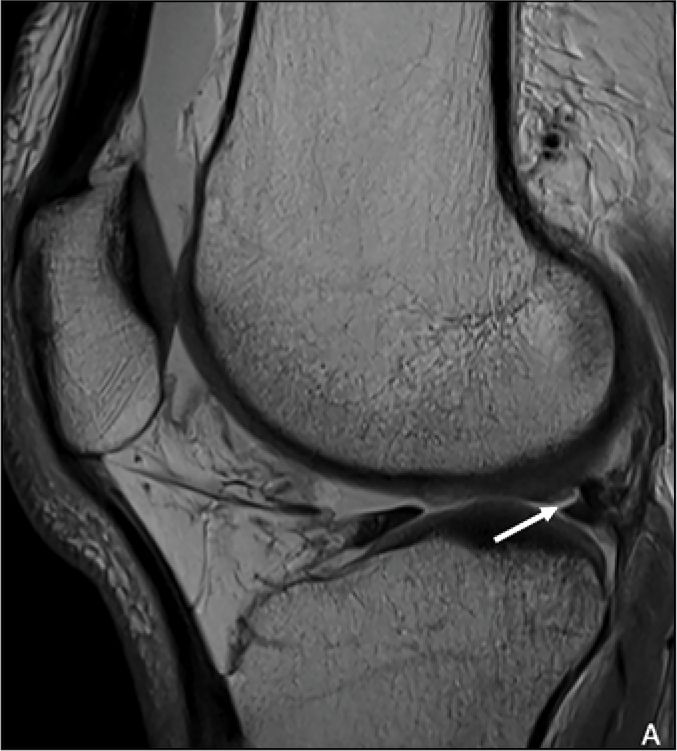

This study assesses MRI's utility in distinguishing lateral meniscal oblique radial tears from other meniscal tears in patients with ACL injury.